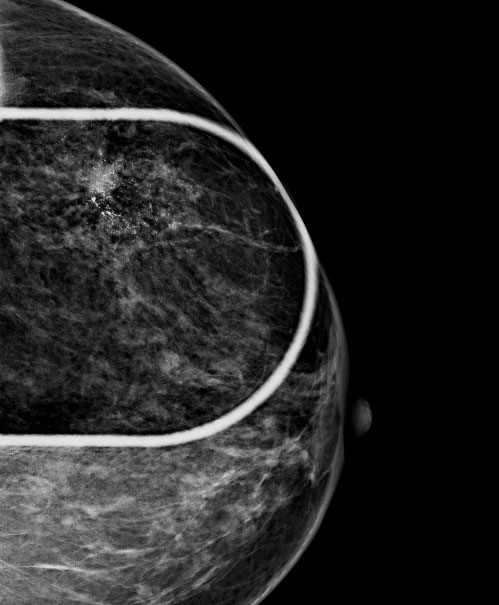

Durch die höhere Kontrastauflösung bei einem höheren Kontrast-Rausch-Verhältnis wird die Erkennungsrate von malignitätsverdächtigen Veränderungen deutlich verbessert. Der Radiologe kann auf hochauflösenden 5 MP-Monitoren die Dichte, Form und Kontur von Gewebearealen wesentlich exakter differenzieren und so gutartige von bösartigen Herdbefunden sicherer unterscheiden. Im Speziellen sind Mikroverkalkungen auch bei der dichten Brust besser zu analysieren.

Die Diagnosesicherheit und Möglichkeit einer Brustkrebsfrüherkennung durch die Mammographie, hängt von der Dichte des Brustdrüsengewebes ab. Einteilung der Dichtegrade wurde vom American College of Radiology (ACR) übernommen.

Bei einem Dichtegrad 3 sinkt die Sensivität der Mammographie deutlich, bei Dichtegrad 4 liegt sie unter 50 %. Durch gleichzeitigen Einsatz der Ultraschalluntersuchung wird die Sicherheit in der Diagnoseerstellung jedoch wieder auf

ca. 90 % angehoben.

40 % der Mammakarzinome weisen Mikroverkalkungen auf. Mikrokalzifikationen sind auch bei sehr dichtem Brustgewebe immer sichtbar. Eine Mammographie sollte daher ab dem 40. Lebensjahr die primäre Untersuchungsmethode sein.